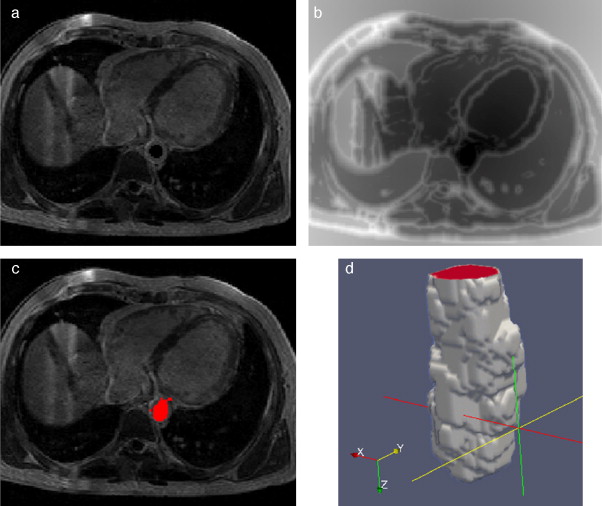

En la figura 15 se presentan los resultados obtenidos por cada etapa de procesamiento en IRM cardiovascular. Las imágenes médicas utilizadas tienen formato DICOM [39] , con 59 cortes de tamaño 192 × 192 pixels, voxel spacing: 1,5625 × 1,5625 × 2,5 mm . Por efectos de visualización, solamente se presenta uno de los cortes axiales de la imagen 3D.

Preproceso y segmentación el volumen del ventrículo izquierdo. (a) Corte axial ...

Figura 15.

Preproceso y segmentación el volumen del ventrículo izquierdo. (a) Corte axial de la IRM cardiovascular original. (b) Imagen (a) filtrada con difusión anisotrópica. (c) Imagen gradiente obtenida a partir de (b). (d) Imagen Watershed con segmentos etiquetados obtenida a partir de (c). (e) Selección del segmento del ventrículo izquierdo empleando umbralización.

En la figura 16 se presenta el volumen final del ventrículo izquierdo con el inicio de la válvula aórtica (fig. 16 .a), el modelo final suavizado visualizado en ParaView (fig. 16 .b), el modelo en sólido visualizado en Autodesk Inventor (fig. 16 .c), el modelo en malla visualizado en GiD (fig. 16 .d) y el modelo discreto con los elementos finitos realizado con Abaqus (fig. 16 .e). Estos modelos han sido obtenidos a partir de IRM cardiovascular de un paciente con cardiopatía isquémica. Obsérvese que la protuberancia presente en la zona superior derecha del ventrículo izquierdo constituye una zona de necrosis conocida como cicatriz isquémica, la cual es alojada en el músculo del miocardio.

Vista tridimensional de ventrículo izquierdo. (a) Volumen original visualizado ...

Figura 16.

Vista tridimensional de ventrículo izquierdo. (a) Volumen original visualizado con ParaView. (b) Volumen original suavizado con morfología matemática visualizado con ParaView. (c) Sólido del volumen generado con Autodesk Inventor. (d) Mallado del volumen generado con GiD. (e) Modelo discreto con el método de elementos finitos generado con Abaqus empleando condiciones de contorno de prueba.